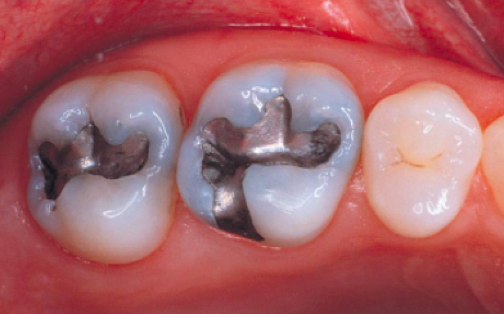

• La dent peut être obturée au cours de la séance à l’aide d’un amalgame. Il est peu esthétique, est utilisé depuis 150 ans. Appelé à tord « plombage », l’amalgame ne contient pas de plomb. Il est composé d’un alliage d’argent, d’étain et de cuivre associés à du mercure. Il est de nos jours l’objet de nombreuses controverses et son utilisation requiert certaines précautions comme chez la femme enceinte.

• Le composite, de couleur identique à celle de la dent, est une résine renforcée de particules minérales.

• En céramique en restaurant la dent grâce à des inlays/onlays